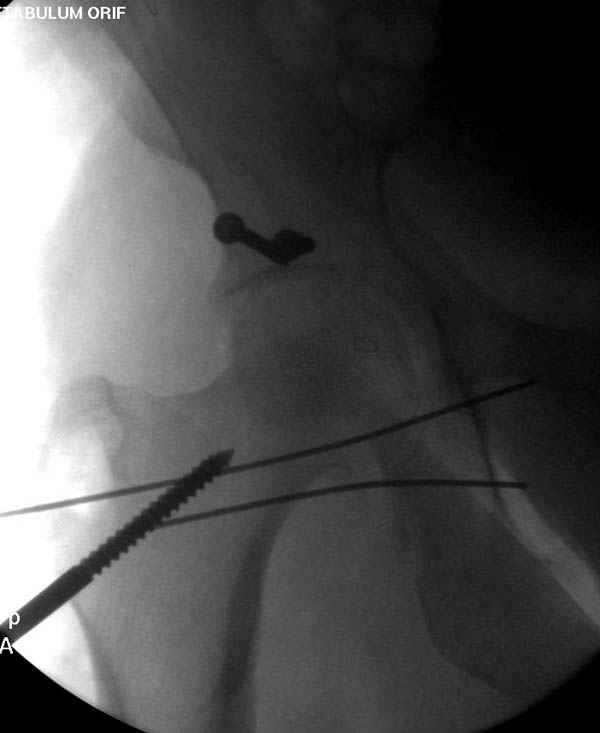

Имя     : 3 Proximal hum+acetabulum CRM.jpg

Url     : http://weborto.net:8080/pipermail/ortho/attachments/20071130/be03ce6b/attachment-0005.jpg